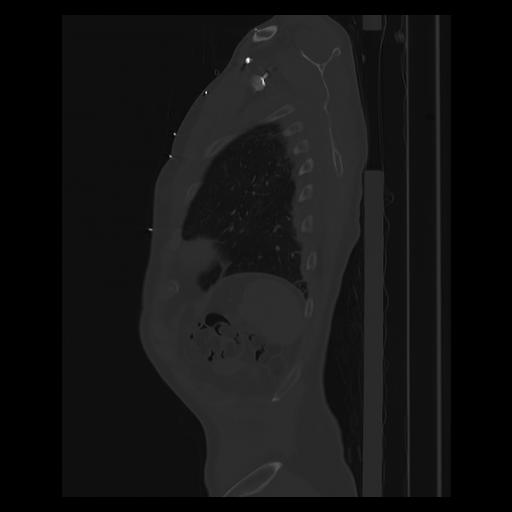

33 PULMON,CE,Sagittal,3.000,PULMON,Sagittal,